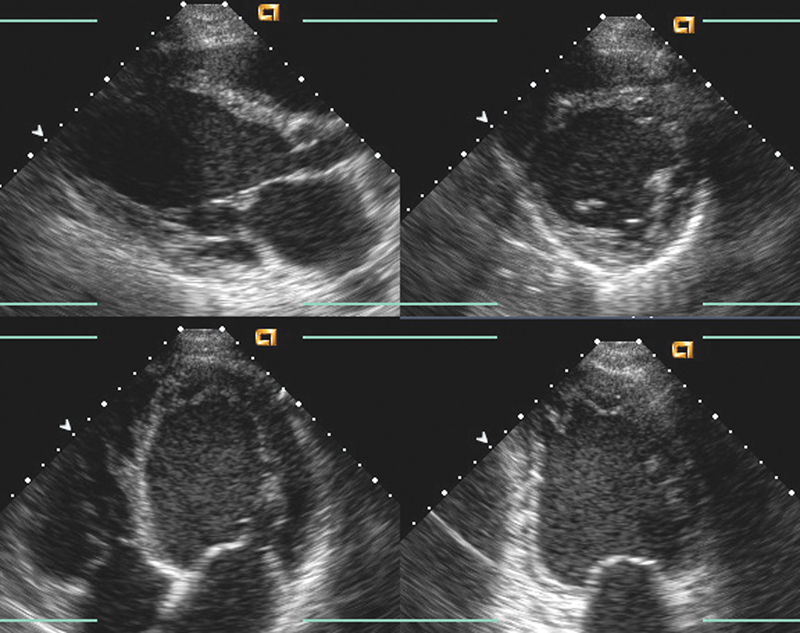

فحوصات تشخيصية لبعض امراض القلب والشرايين التاجية